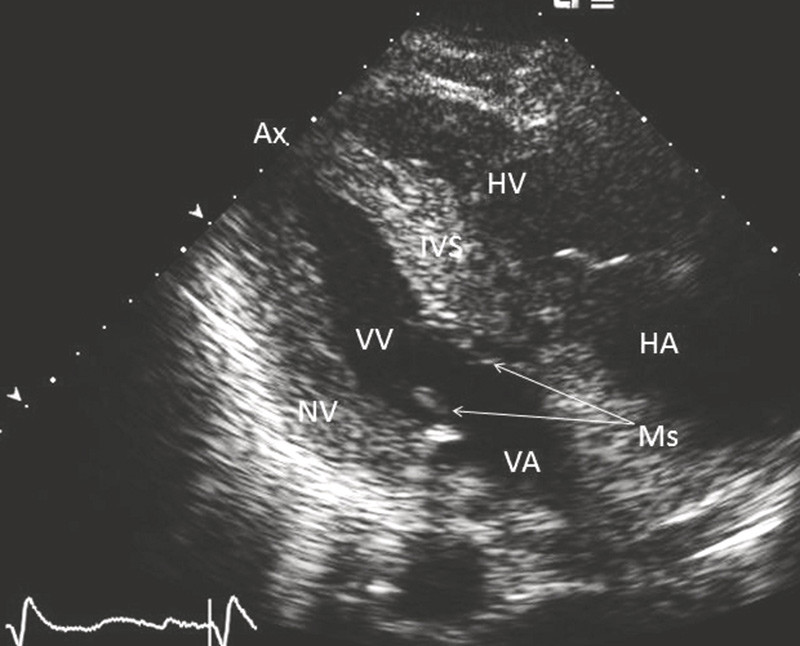

We submitted the patient to further echocardiography. There was no pericardial fluid accumulation. The left ventricle displayed clear general hypertrophy with wall thicknesses of 1.6 – 1.7 (normal wall thicknesses ≤ 1.1 cm) (Fig. 2). Because of the hypertrophy the ventricle had a small cavity with an end-diastolic diameter of 3.9 cm (normal range 4.2 – 5.9 cm). The ventricle displayed hypernormal cross-sectional contractility in all sections with no sign of infarction sequelae, while the longitudinal contractility was reduced. The ventricle’s ejection fraction showed a normal value of 65 %. There was no systolic intracavitary obstruction in the ventricle. The mitral valve had somewhat thickened leaflets with good mobility and slight leakage.

Blood flow velocities through the mitral valve coupled with tissue velocities at the mitral rings indicated elevated filling pressure in the left ventricle. The aortic valve was tricuspid with thickened cusps that displayed good opening mobility, and an opening area of at least 1.5 cm² was calculated. The mean and maximum gradients over the aortic valve were found by Doppler examination to be 10 and 17 mm Hg, respectively. There was also a minimal leakage at the commissure between the three aortic cusps. The right ventricle had normal internal dimensions and displayed good contractility. The inferior vena cava was enlarged, however, and its calibre variations were reduced to only 20 % during normal respiration. This indicated elevated filling pressure in the right ventricle. There was moderate tricuspid leakage. The maximum gradient over the tricuspid valve was 30 mm Hg. Added to the elevated atrial pressure, this indicated a systolic pulmonary artery pressure of 40 – 45 mm Hg. The thickness of the free right ventricular wall was measured at 1.1 cm (normal thickness ≤ 0.5 cm). The pulmonary valve was normal. Both atria were moderately enlarged. The atrial septum was thickened to 1.1 cm. The myocardium of both ventricles had a pronounced granular expression (Fig. 2).

Figure 2  Echocardiography (slightly modified parasternal two-chamber view) shows left ventricle with hypertrophied walls…

Figure 2 Echocardiography (slightly modified parasternal two-chamber view) shows left ventricle with hypertrophied walls with pronounced granular expression. Ax = apex, HA = right atrium, HV = right ventricle, IVS = interventricular septum, Ms = mitral leaflet, NV = lower wall, VA = left atrium, VV = left ventricle.

The patient had significant hypertrophy of the left ventricle, and in his case it was difficult to attribute this to arterial hypertension or the relatively mild aortic stenosis. The slightly elevated systolic pulmonary artery pressure could be attributed to left-sided heart failure and could not explain the significant hypertrophy of the right ventricular free wall. The fact that both ventricles showed hypertrophy pointed rather to restrictive cardiomyopathy, and the overall echocardiographic findings gave rise to suspicion of cardiac amyloidosis. The two most common causes of amyloid deposition in the heart are overproduction of monoclonal immunoglobulin light chains (AL amyloidosis) and transthyretin-related disease (familial and senile type) (1).

Revealing the causes of heart failure is important for the choice of treatment and assessment of the prognosis. In our patient, arterial hypertension was probably not the causal factor behind progressive heart failure, as was initially believed. On the contrary, the echocardiogram showed changes that are distinctive for cardiac amyloidosis (Fig. 2). Further tests yielded no evidence of AL amyloidosis, while the 99mTc-DPD scintigram showed myocardial changes consistent with transthyretin-related cardiac amyloidosis (Fig. 3). There was no familial occurrence of heart failure, and the patient probably had the far more common senile form of transthyretin-related disorder. Representative biopsies might have provided further confirmation of the disease. However, extracardiac biopsies have a low sensitivity for transthyretin-related amyloidosis. Referring our patient to a university hospital for a heart biopsy appeared unnecessary since the echocardiogram and scintigram findings made us sure of our diagnosis. Any biopsy findings would hardly have changed our treatment of this sick patient.